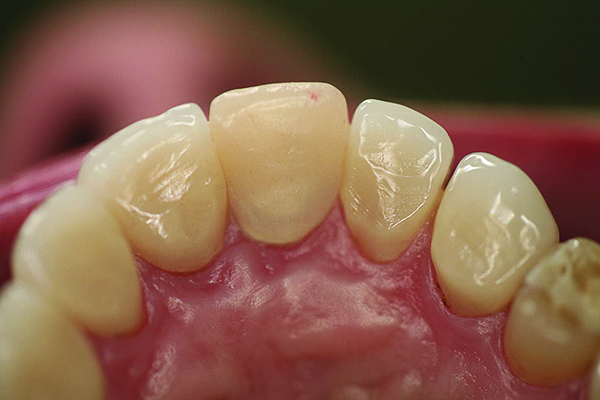

Figure 5 and Figure 6. All-ceramic restorations (Figure 5) and opposing dentition wear (Figure 6) produced by all-ceramic feldspathic restorations.

Figure 5